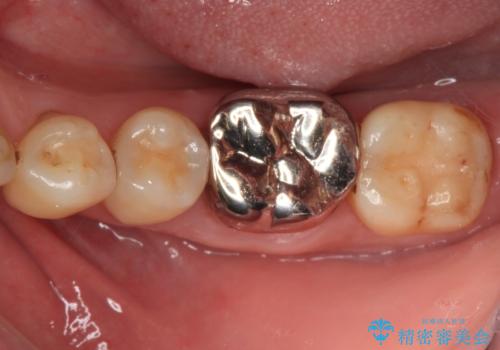

- 人と話す際に、下顎の奥にある銀歯が目立って気になるとのことで来院された患者様です。

左右の奥歯に銀歯のクラウンが装着されていたため、銀歯除去後に仮歯に置き換え、フルジルコニアクラウンにて補綴治療を行うこととしました。